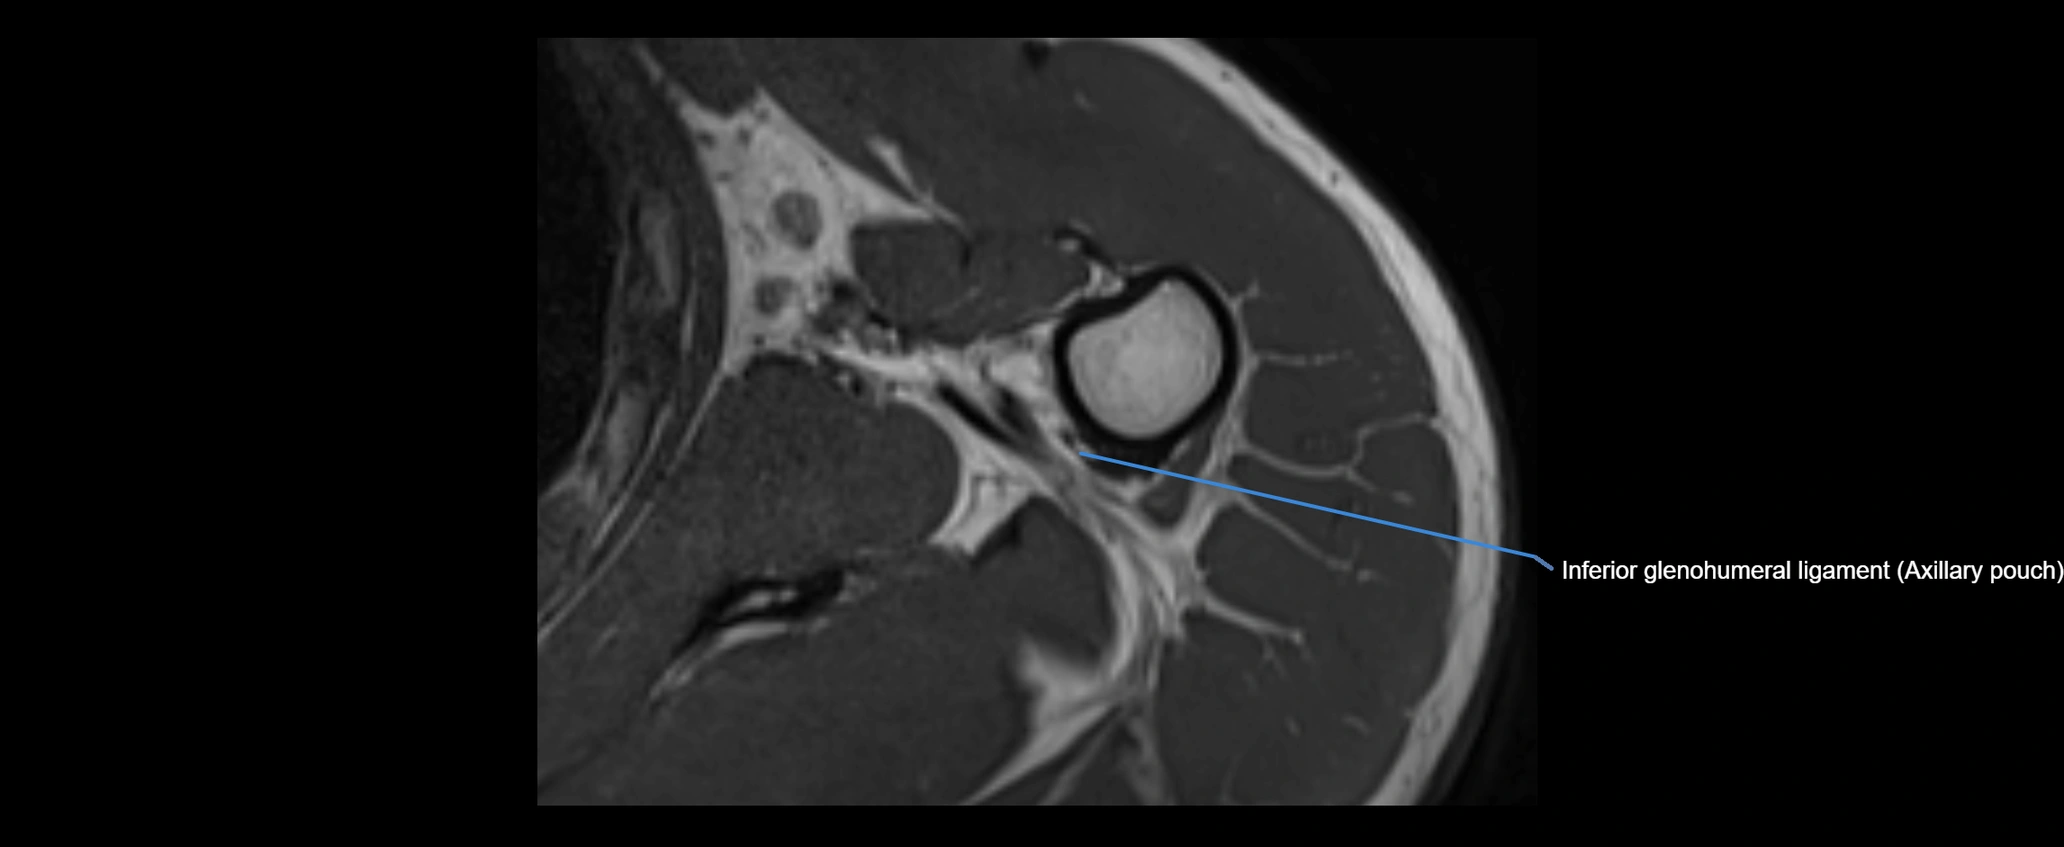

MRI images

image